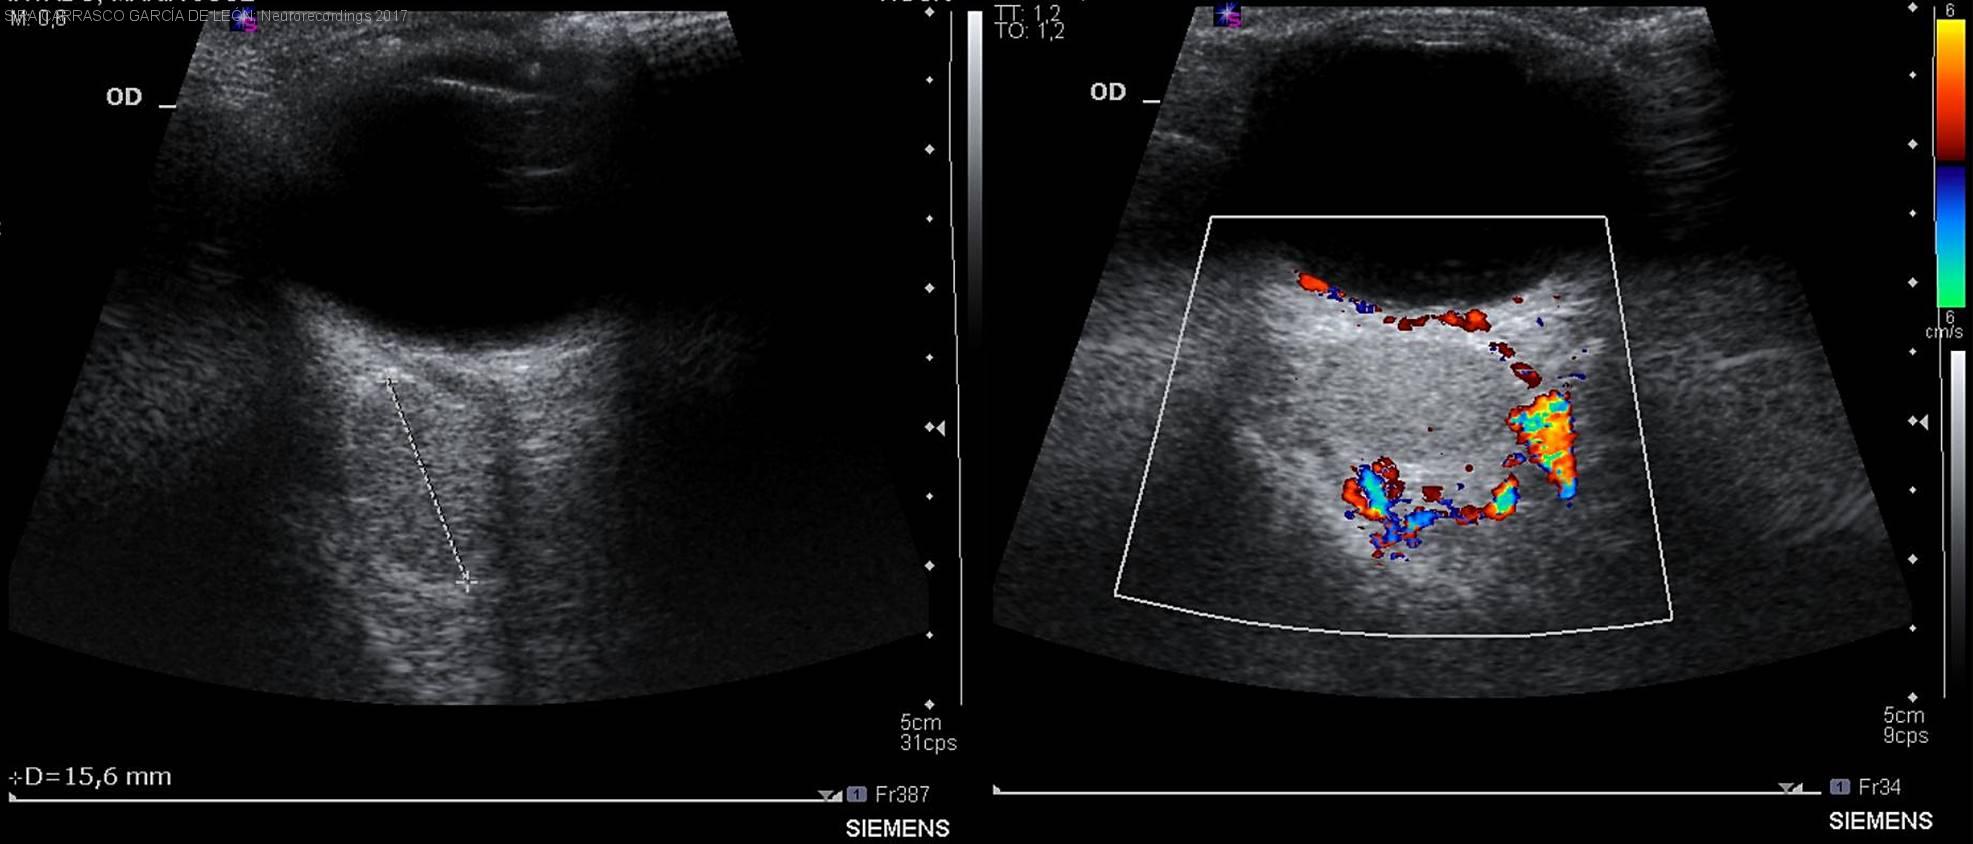

Diagnóstico final: Hemangioma Cavernoso Orbitario del adulto

Mujer de 39 años con antecedentes de sinusitis crónica, cuyo embarazo transcurrió sin incidencias y el parto fue vaginal sin complicaciones. Consulta en el tercer mes postparto por ptosis palpebral derecha de lenta progresión. A la exploración...